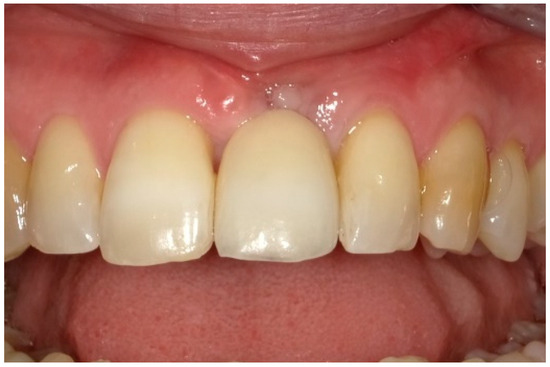

| Tpre | T12 | Tpre | T12 | Tpre | T12 | |

| Mesial papilla | 1 | 1 | 0 | 0 | 2 | 2 |

| Distal papilla | 1 | 1 | 0 | 0 | 2 | 1 |

| Curvature of the facial mucosa | 1 | 1 | 2 | 2 | 1 | 2 |

| Level of the facial mucosa | 0 | 2 | 2 | 1 | 1 | 2 |

| Root convexity/soft tissue color and texture | 0 | 1 | 2 | 2 | 0 | 1 |

| Total | 3 | 6 | 6 | 5 | 6 | 8 |